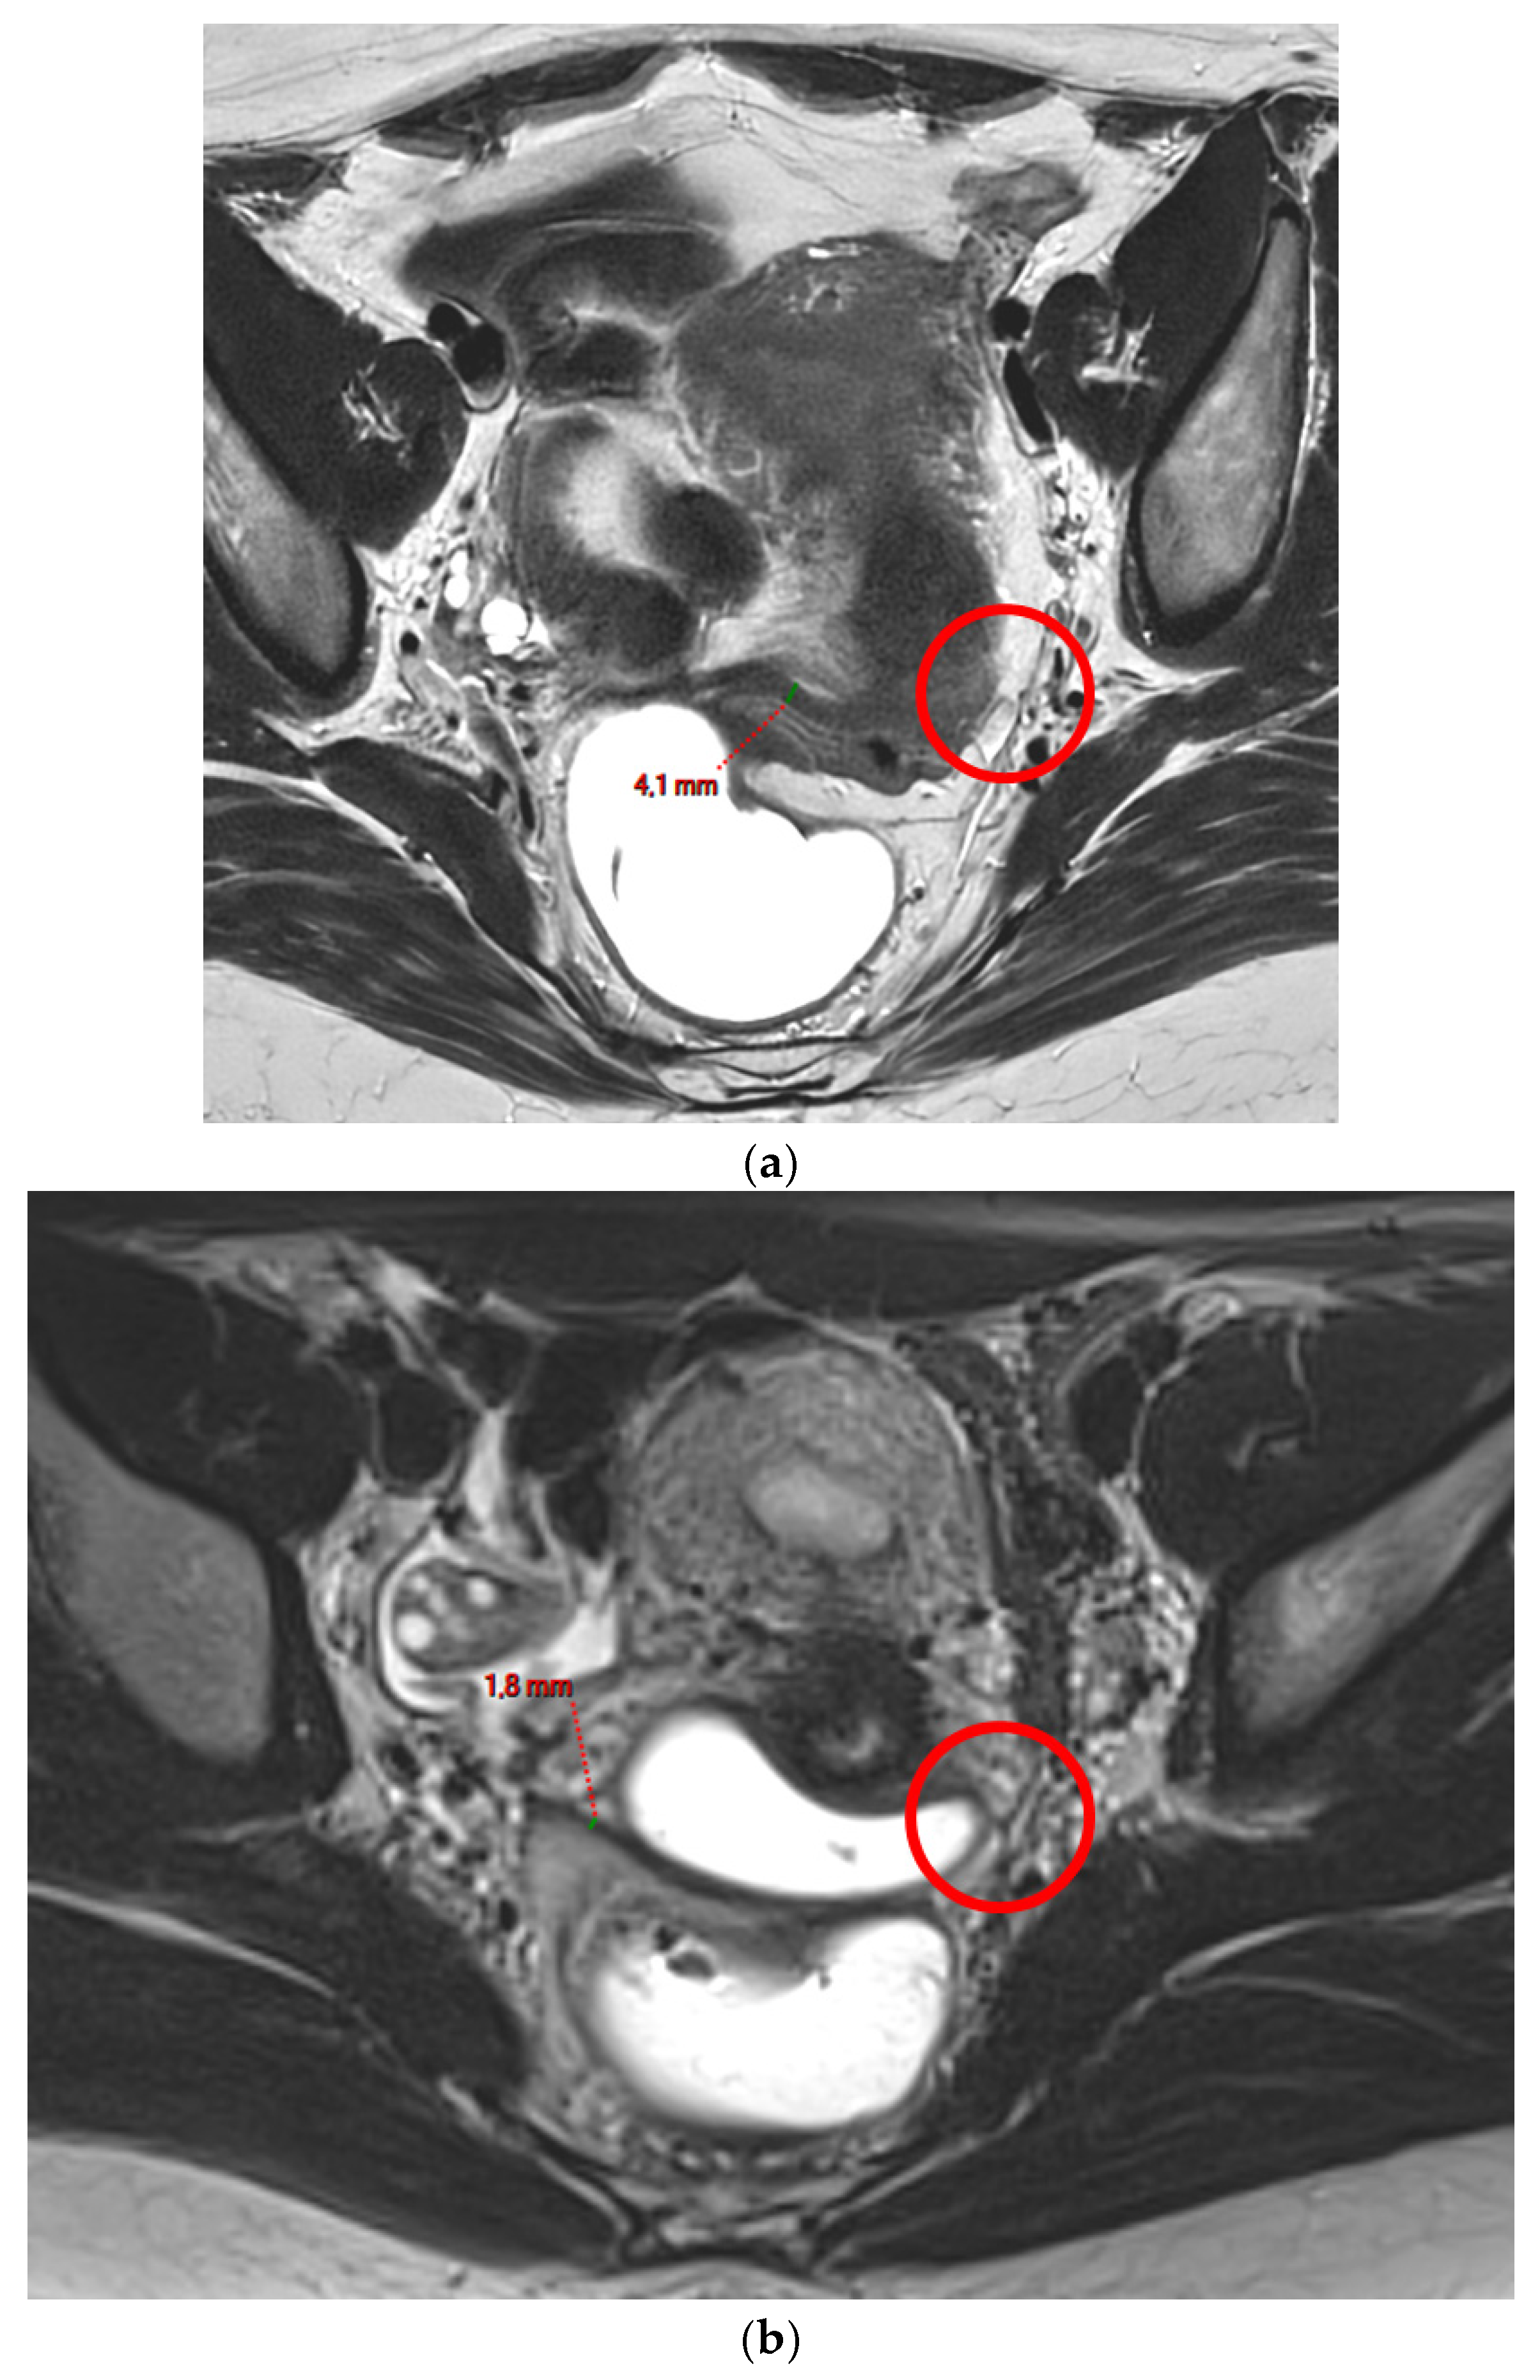

A type 1 USL (Figure 1) is not visible on MRI scans.

Figure 1. Pelvic MRI scans of two patients with non-visible left USLs (HTD type 1). (a) Axial T2WI shows a visible and measurable right USL but a non-visible left USL (red circle). (b) Axial T2WI shows a visible and measurable right USL but a non-visible left USL (red circle).